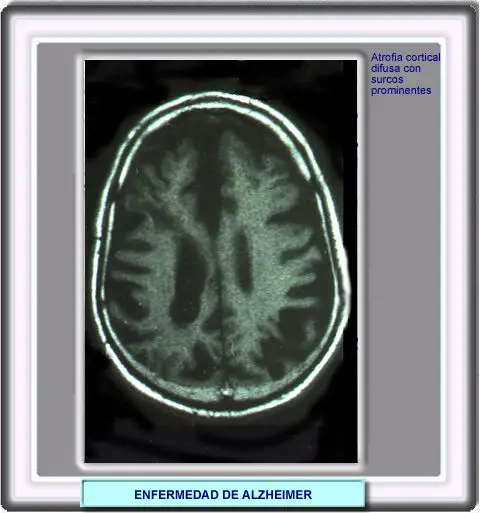

La resonancia magnética y la tomografía computarizada permiten diagnosticar la enfermedad de Alzheimer con una exactitud del 85 al 95%.

En las RM se suelen observar atrofias en la región mesial temporal y lesiones difusas cubcorticales. Sin embargo, en ocasiones no se observan hallazgos anormales, en cuyo caso, son necesarios estudios funcionales con 18F-fluroglucosa por tomografía de emisión de positrones